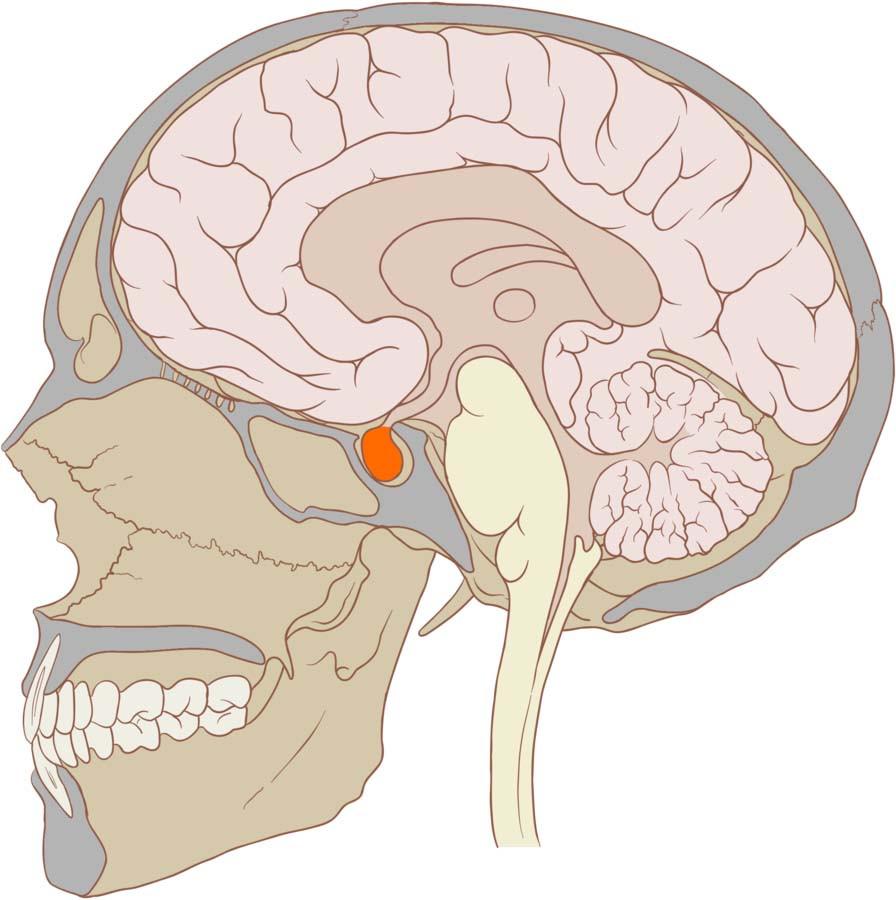

The pituitary gland is only about the size of a pea, but it does an incredible job of controlling the rest of the endocrine (hormonal) system. It handles critical bodily functions ranging from managing body temperature, regulating sleep patterns, controlling urine amounts and dictating one’s general wellbeing as it controls other hormonal glands. This is why the pituitary gland is variously referred to as the master gland. It is safely positioned in a cavity at the base of the brain adjacent to the hypothalamus which in turn controls the pituitary gland through signals from the brain.

Connection Between The Hypothalamus And The Pituitary